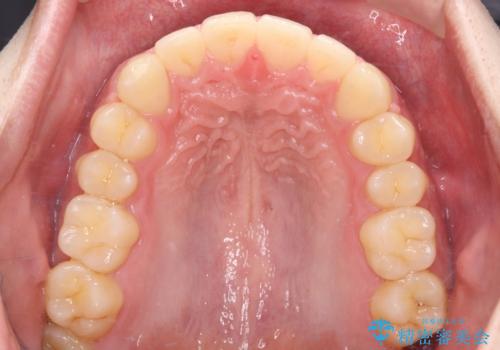

上顎中切歯間の隙間の他にもフロスが抵抗なく入るスペースが上顎は数か所ありました。スペースを閉じ下顎の歯列弓との調和をとるためIPRを行いました。